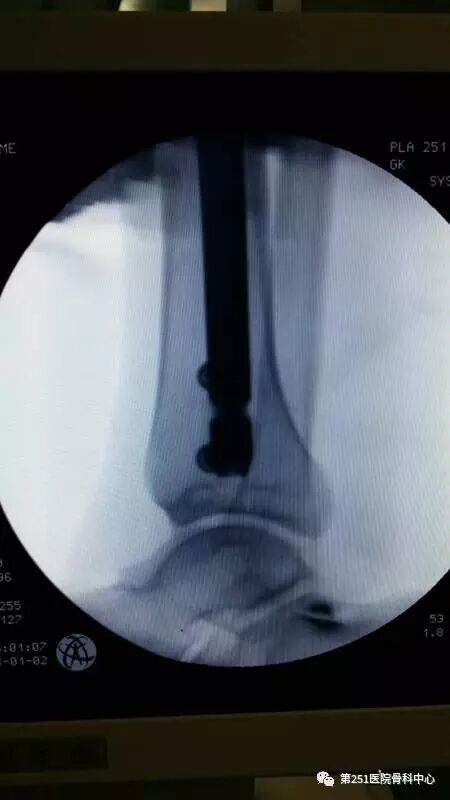

病例6:男性,39岁,车祸伤SchatzkerⅥ型胫骨平台骨折。

![]()